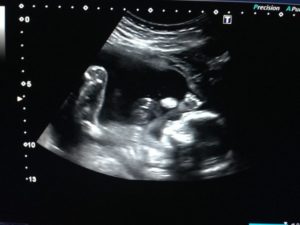

Увидеть двойняшек на мониторе при ультразвуке можно начиная с самых ранних сроков. В это время малыши только-только начинают оформляться, и на экране видно просто 2 темных пятнышка. Но у каждого из них уже есть маленькое сердечко, которое вполне реально услышать.

Если будущая мама впервые узнала о двойняшках на первом плановом ультразвуке в 9-11 недель, она может увидеть полноценных эмбрионов длиной в 4,5-4,8 см.

Малыши в это время уже двигаются, у них сформированы внутренние органы, появились пальчики. К 14-й неделе плоды уже достигают в длину 12 см – в это время мамин животик начинает активно расти.

В 12 недель длина каждого из близнецов – около 6 см, вес – приблизительно 8 гр.

Многоплодная беременность на УЗИ. Близнецы.Многоплодная беременность на УЗИ. Близнецы.